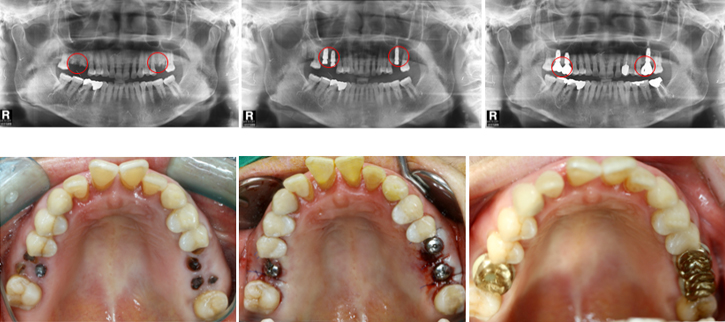

우선 CT촬영 등을 통해 구강상태를 정밀 진단 후 환자의 상태에 따라 맞는 치료 계획을 세웁니다. 구체적인 임플란트 시술 과정과 기간은 환자의 상태에 따라 달라질 수 있다고 해요.

2단계 1차 수술

이 과정은 픽스쳐를 잇몸뼈에 심는 과정인데요. (픽스쳐란 치아의 뿌리 역할을 하는 것을 말함)

3단계 2차 수술

픽스쳐와 보철물을 견결할 공간을 만들기 위해 진행하는 수술로 잇몸밖으로 나사를 연결하는 과정인데요. 1차 수술 이후 식립한 임플란트 픽스쳐가 자연 치아의 뿌리처럼 잇몸뼈에 단단하게 고정될 때까지 기다려야하며 픽스쳐가 치조골과 단단히 결합해 안정화되어야 2차 수술을 진행할 수 있다고 해요.

4단계 크라운제작 및 교정

수술부위가 아물면 임플란트 지주대와 주변치아를 본을 뜬뒤, 치아 형태의 보철물인 크라운 제작을 한다고 해요. 크라운 제작 기간은 보통 일주일 정도라고 해요. 보철물이 완성되면 크라운을 임플란트 지대주에 장착해 고정시킵니다고 해요. 그 다음 음식을 씹을 때 불편함이 없도록 조정한다고 해요.